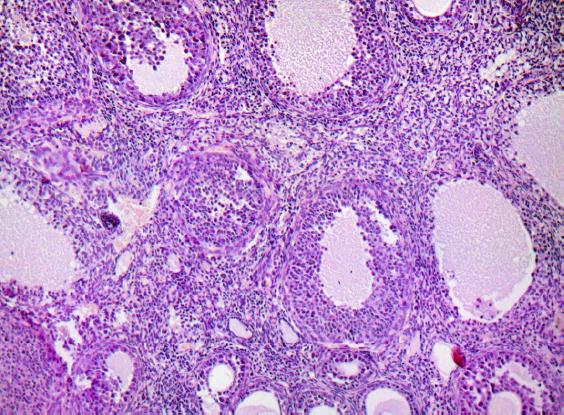

Обсуждение. В яичниках потомства первой экспериментальной группы С-50 наблюдаются стойкие морфологические изменения: увеличение средней площади коркового вещества, уменьшение показателей площади мозгового вещества, увеличение среднего количества желтых тел, увеличение среднего количества лютеиновых клеток в желтом теле, снижение суммарного количества фолликулов и атретических тел, свидетельствующие о нарушении процесса фолликулогенеза, увеличение среднего диаметра кровеносных сосудов, демонстрирующие усиление кровообращения. При введении препарата фулвестранта в дозе 100 мкг/кг во второй экспериментальной группе Ф-100 на срезе яичников потомства рассматриваются морфологические изменения в виде увеличения средней площади коркового вещества, уменьшения средней площади мозгового вещества, склерозирования стромального компонента, сопровождающегося перестройкой сосудистой сети с признаками атрезии и кистозного перерождения фолликулярного эпителия во вторичных и третичных фолликулах.